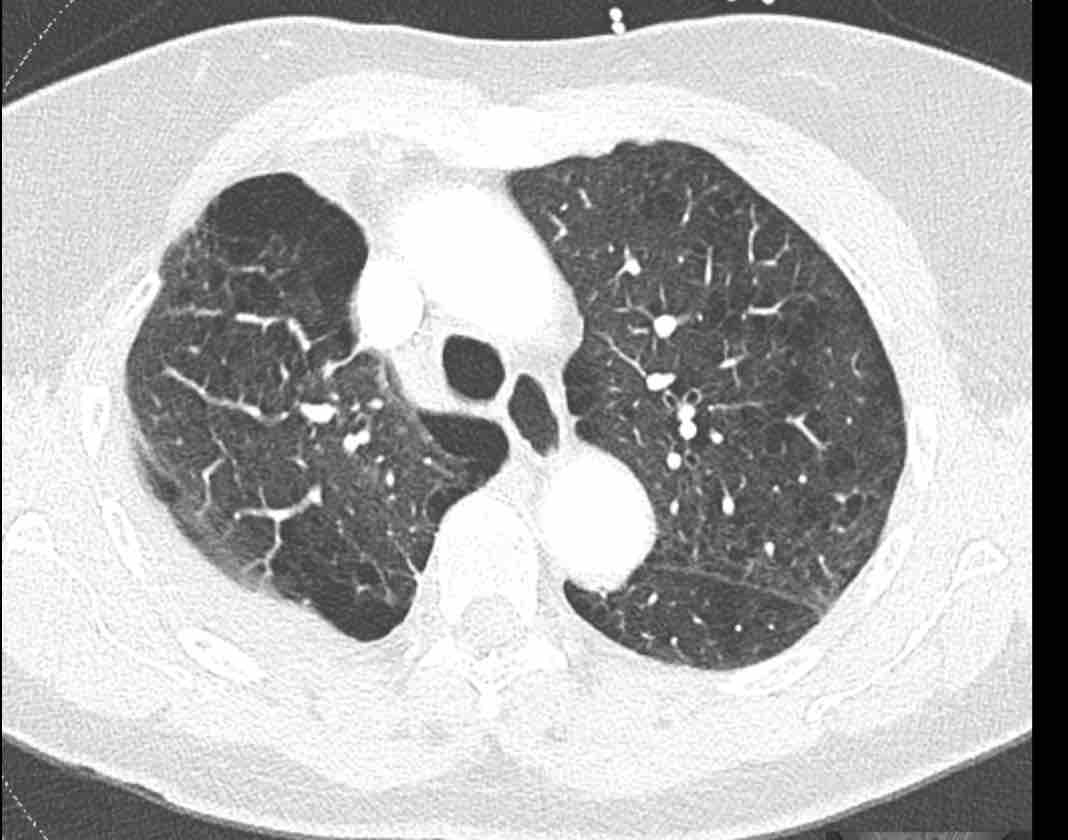

Xoắn phổi

Việc theo dõi đường đi của các phế quản sẽ giúp xác định mô phổi bị di lệch.

Các hình ảnh này của một bệnh nhân nữ 65 tuổi sau khi đã cắt thùy trên phổi phải trước đó.

Trước tiên, hãy cuộn qua các hình ảnh.

Hình ảnh

Theo dõi lần lượt các phế quản giúp xác định mỏm cắt thùy trên phổi phải (RUL), phế quản thùy giữa bị tắc nghẽn và các phế quản thùy dưới còn thông.

Điều này xác định mô phổi bị di lệch xuống dưới chính là thùy giữa phổi phải (RML), thấy rõ nhất trên mặt phẳng đứng dọc.

Thùy giữa phổi phải bị phù nề và không còn được tưới máu.

Ngoài ra còn thấy hình ảnh ứ máu và xẹp phổi ở các phân thùy đáy của thùy dưới phổi phải (RLL), hiện nằm phía trên thùy giữa phổi phải đã bị nhồi máu.